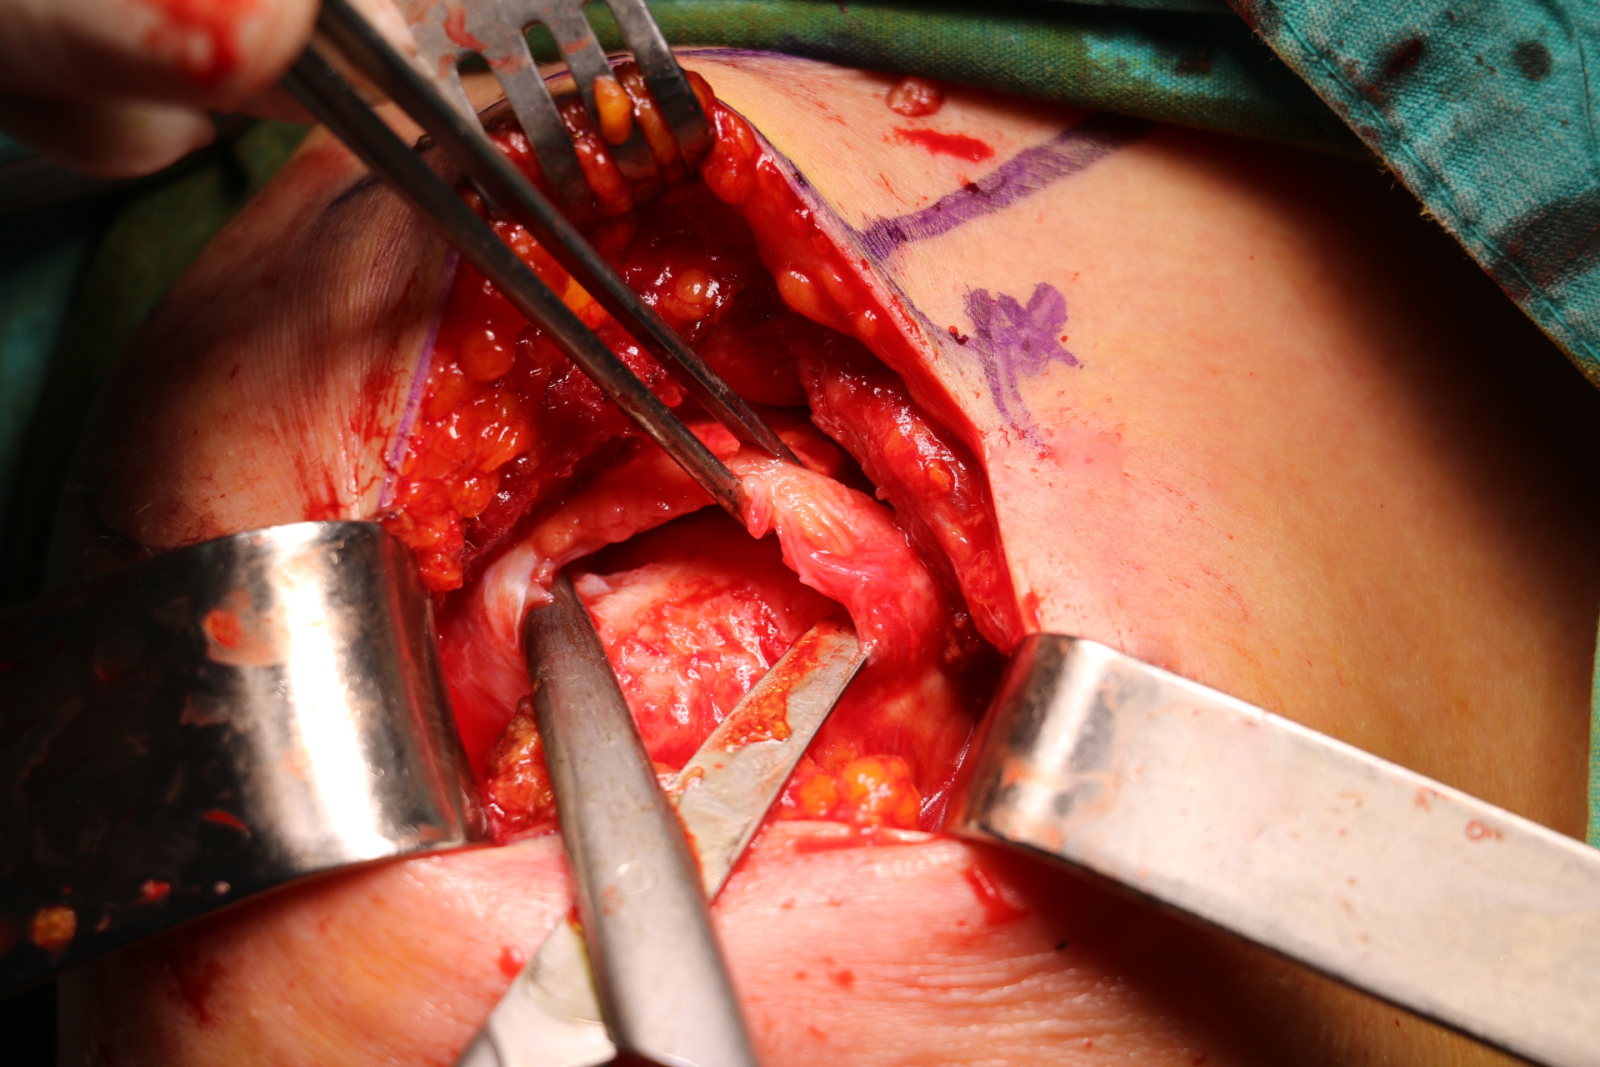

Açık Tendon Onarımı: Bazı durumlarda açık tendon onarımı daha iyi bir seçenek olabilir. Bu tür ameliyatlarda hasar görmüş tendonun kemiğe yeniden bağlanması için daha büyük bir kesi yoluyla çalışılır.

| Rotator manşet yırtığının açık cerrahi tedavisi | |